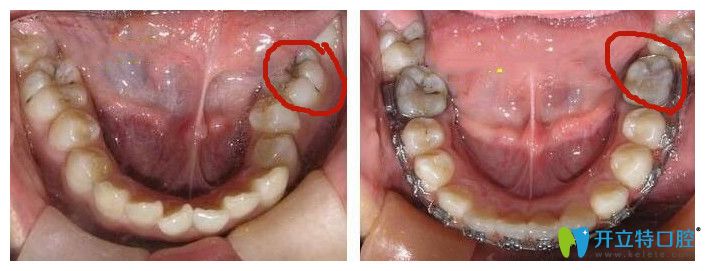

牙齒鎖合圖片

鎖合牙圖片

鎖合牙矯正對(duì)比圖